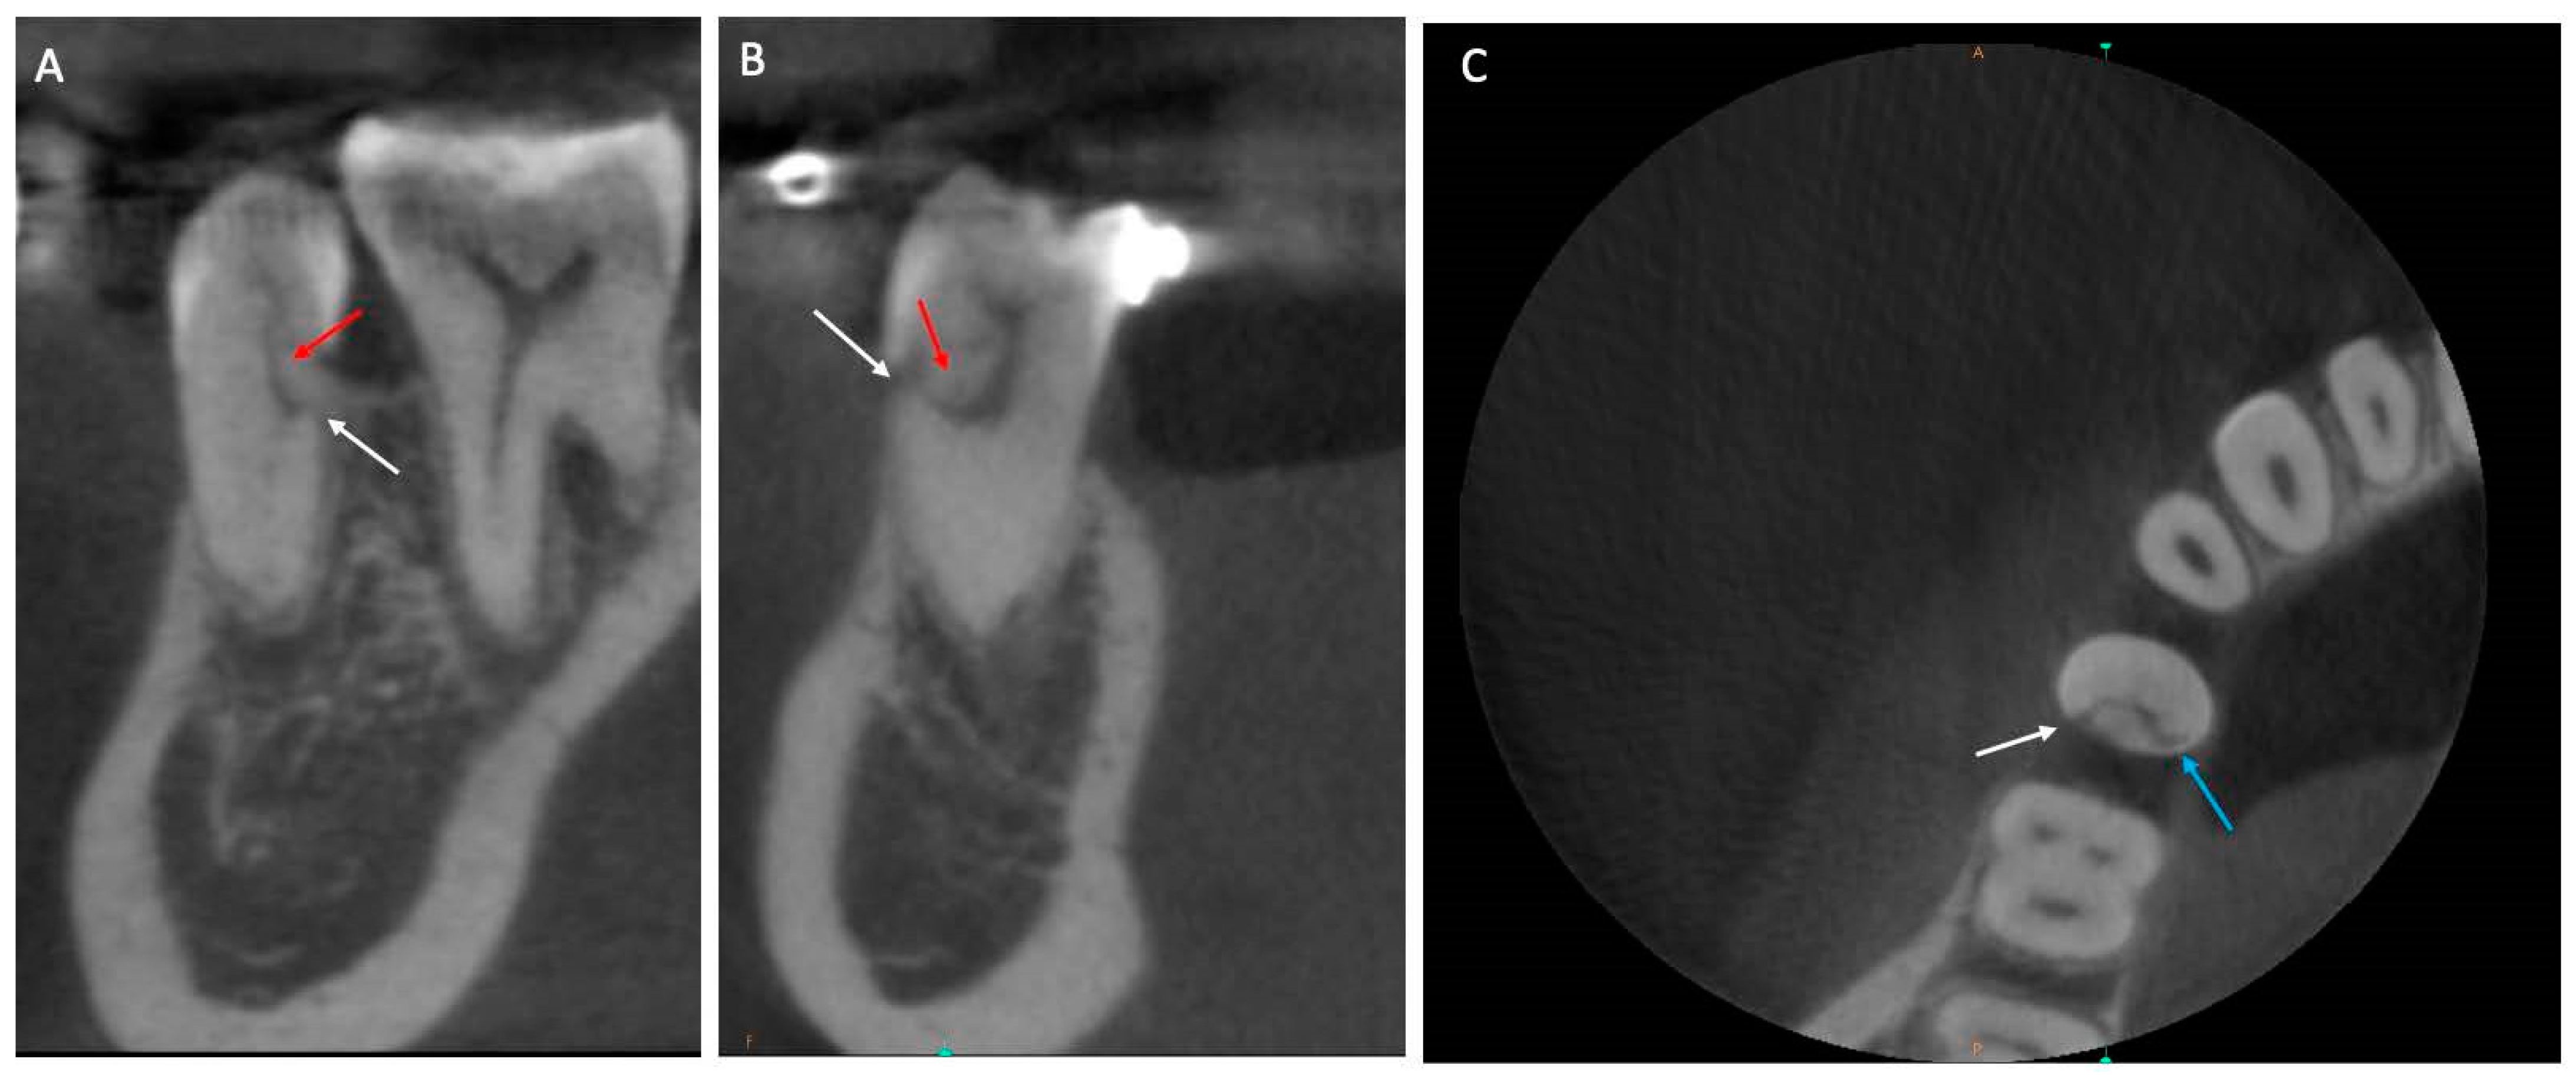

2. Case Presentation